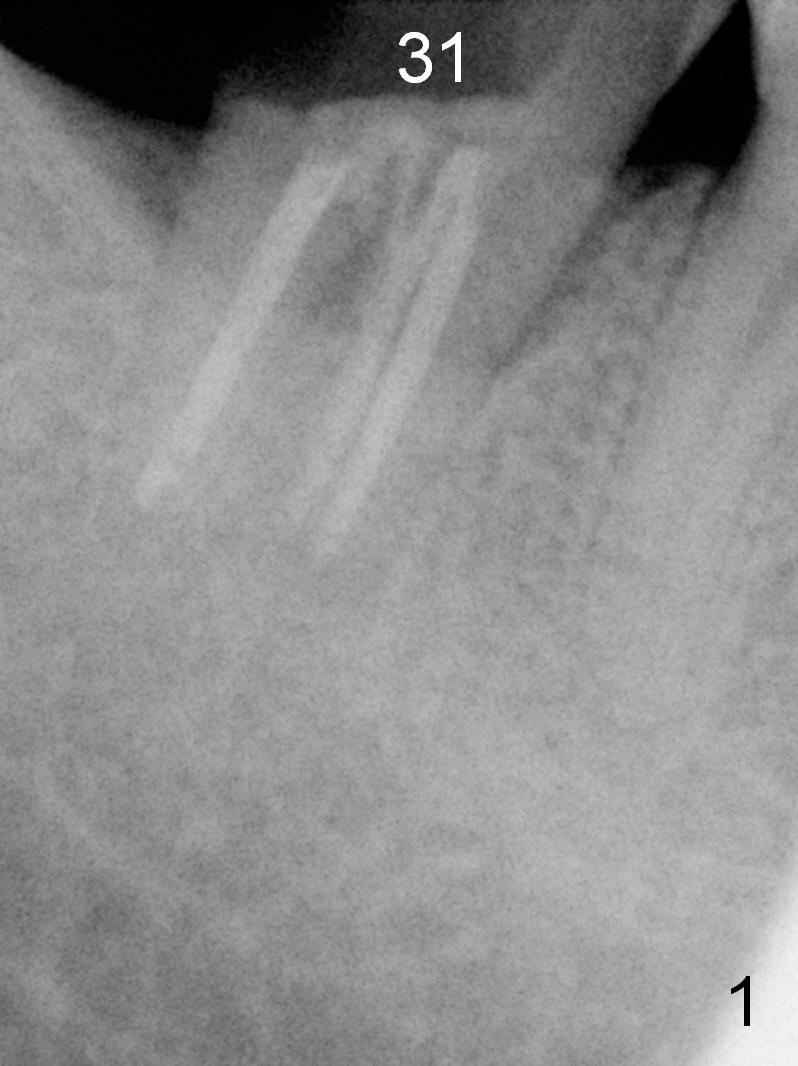

The 61-year-old man is nervous about dentistry. When he returns for #4 implant, he wants an implant at #31 first. Fig.1 shows #31 crown fracture after root canal therapy. Three years after crown placement, there is sign of mesial root fracture (Fig.2 arrowheads). Four years post extraction, bone height is 12 mm (Fig.3 parallel pin 10 mm). An extra wide implant is to be placed, since there is enough bone width. With infiltration anesthesia, the patient feels pain when a 5.4x10 mm drill is being used, 1 mm short of the desirable depth (Fig.4). After Inferior Alveolar Nerve block, the last drill reaches the depth. A 5.9x10 mm implant is placed with insertion torque 50 Ncm (Fig.5 I). A 7.8x4(3) mm cemented abutment (A) is placed immediately. After suturing, the restorative portion of the abutment is covered by the gingiva. It is probably due to over tightening the sutures. It would be ideal to adjust the gingival level before tightening the second suture.